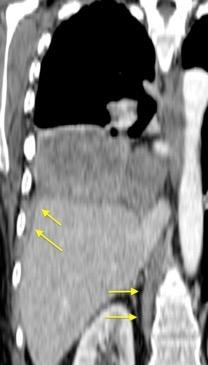

T. mixto de células germinales del testículo izquierdo

Nódulos pulmonares múltiples. (flechas verdes). Masas paratraqueales. (flechas amarillas). Dudoso ensanchamiento retrocrural (flechas negras). sigue….

Ttawfik A et al. Trans-diaphragmatic Pathologies: Anatomical Background and Spread of Disease on cross-sectional Imaging. Current Problems in Diagnostic Radiology. 2021.

T. mixto de células germinales del testículo

izquierdo Metástasis pulmonares. (flechas verdes). Ganglios paratraqueales. (flechas amarillas). Ganglios retroperitoneales (flechas negras)

Tawfik A et al. Trans-diaphragmatic Pathologies: Anatomical Background and Spread of Disease on cross-sectional Imaging. Current Problems in Diagnostic Radiology. 2021.